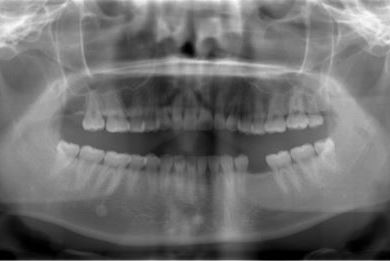

| 性別/年齢 | 女性 / 29歳 | ||||||||||||||||||||||||||||||||

| 主訴 | インプラント治療と、親知らずの抜歯の相談。なるべく安価で、短期間で終了して欲しい。 | ||||||||||||||||||||||||||||||||

| 治療方針 | 欠損部分をインプラント治療にて、機能的・審美的回復を行う。 | ||||||||||||||||||||||||||||||||

| 治療内容 | インプラント1本、メタルボンドセラミッククラウン1本 | ||||||||||||||||||||||||||||||||

| 総治療費 | 252,000円 | ||||||||||||||||||||||||||||||||

| 治療期間 | 11ヶ月 |